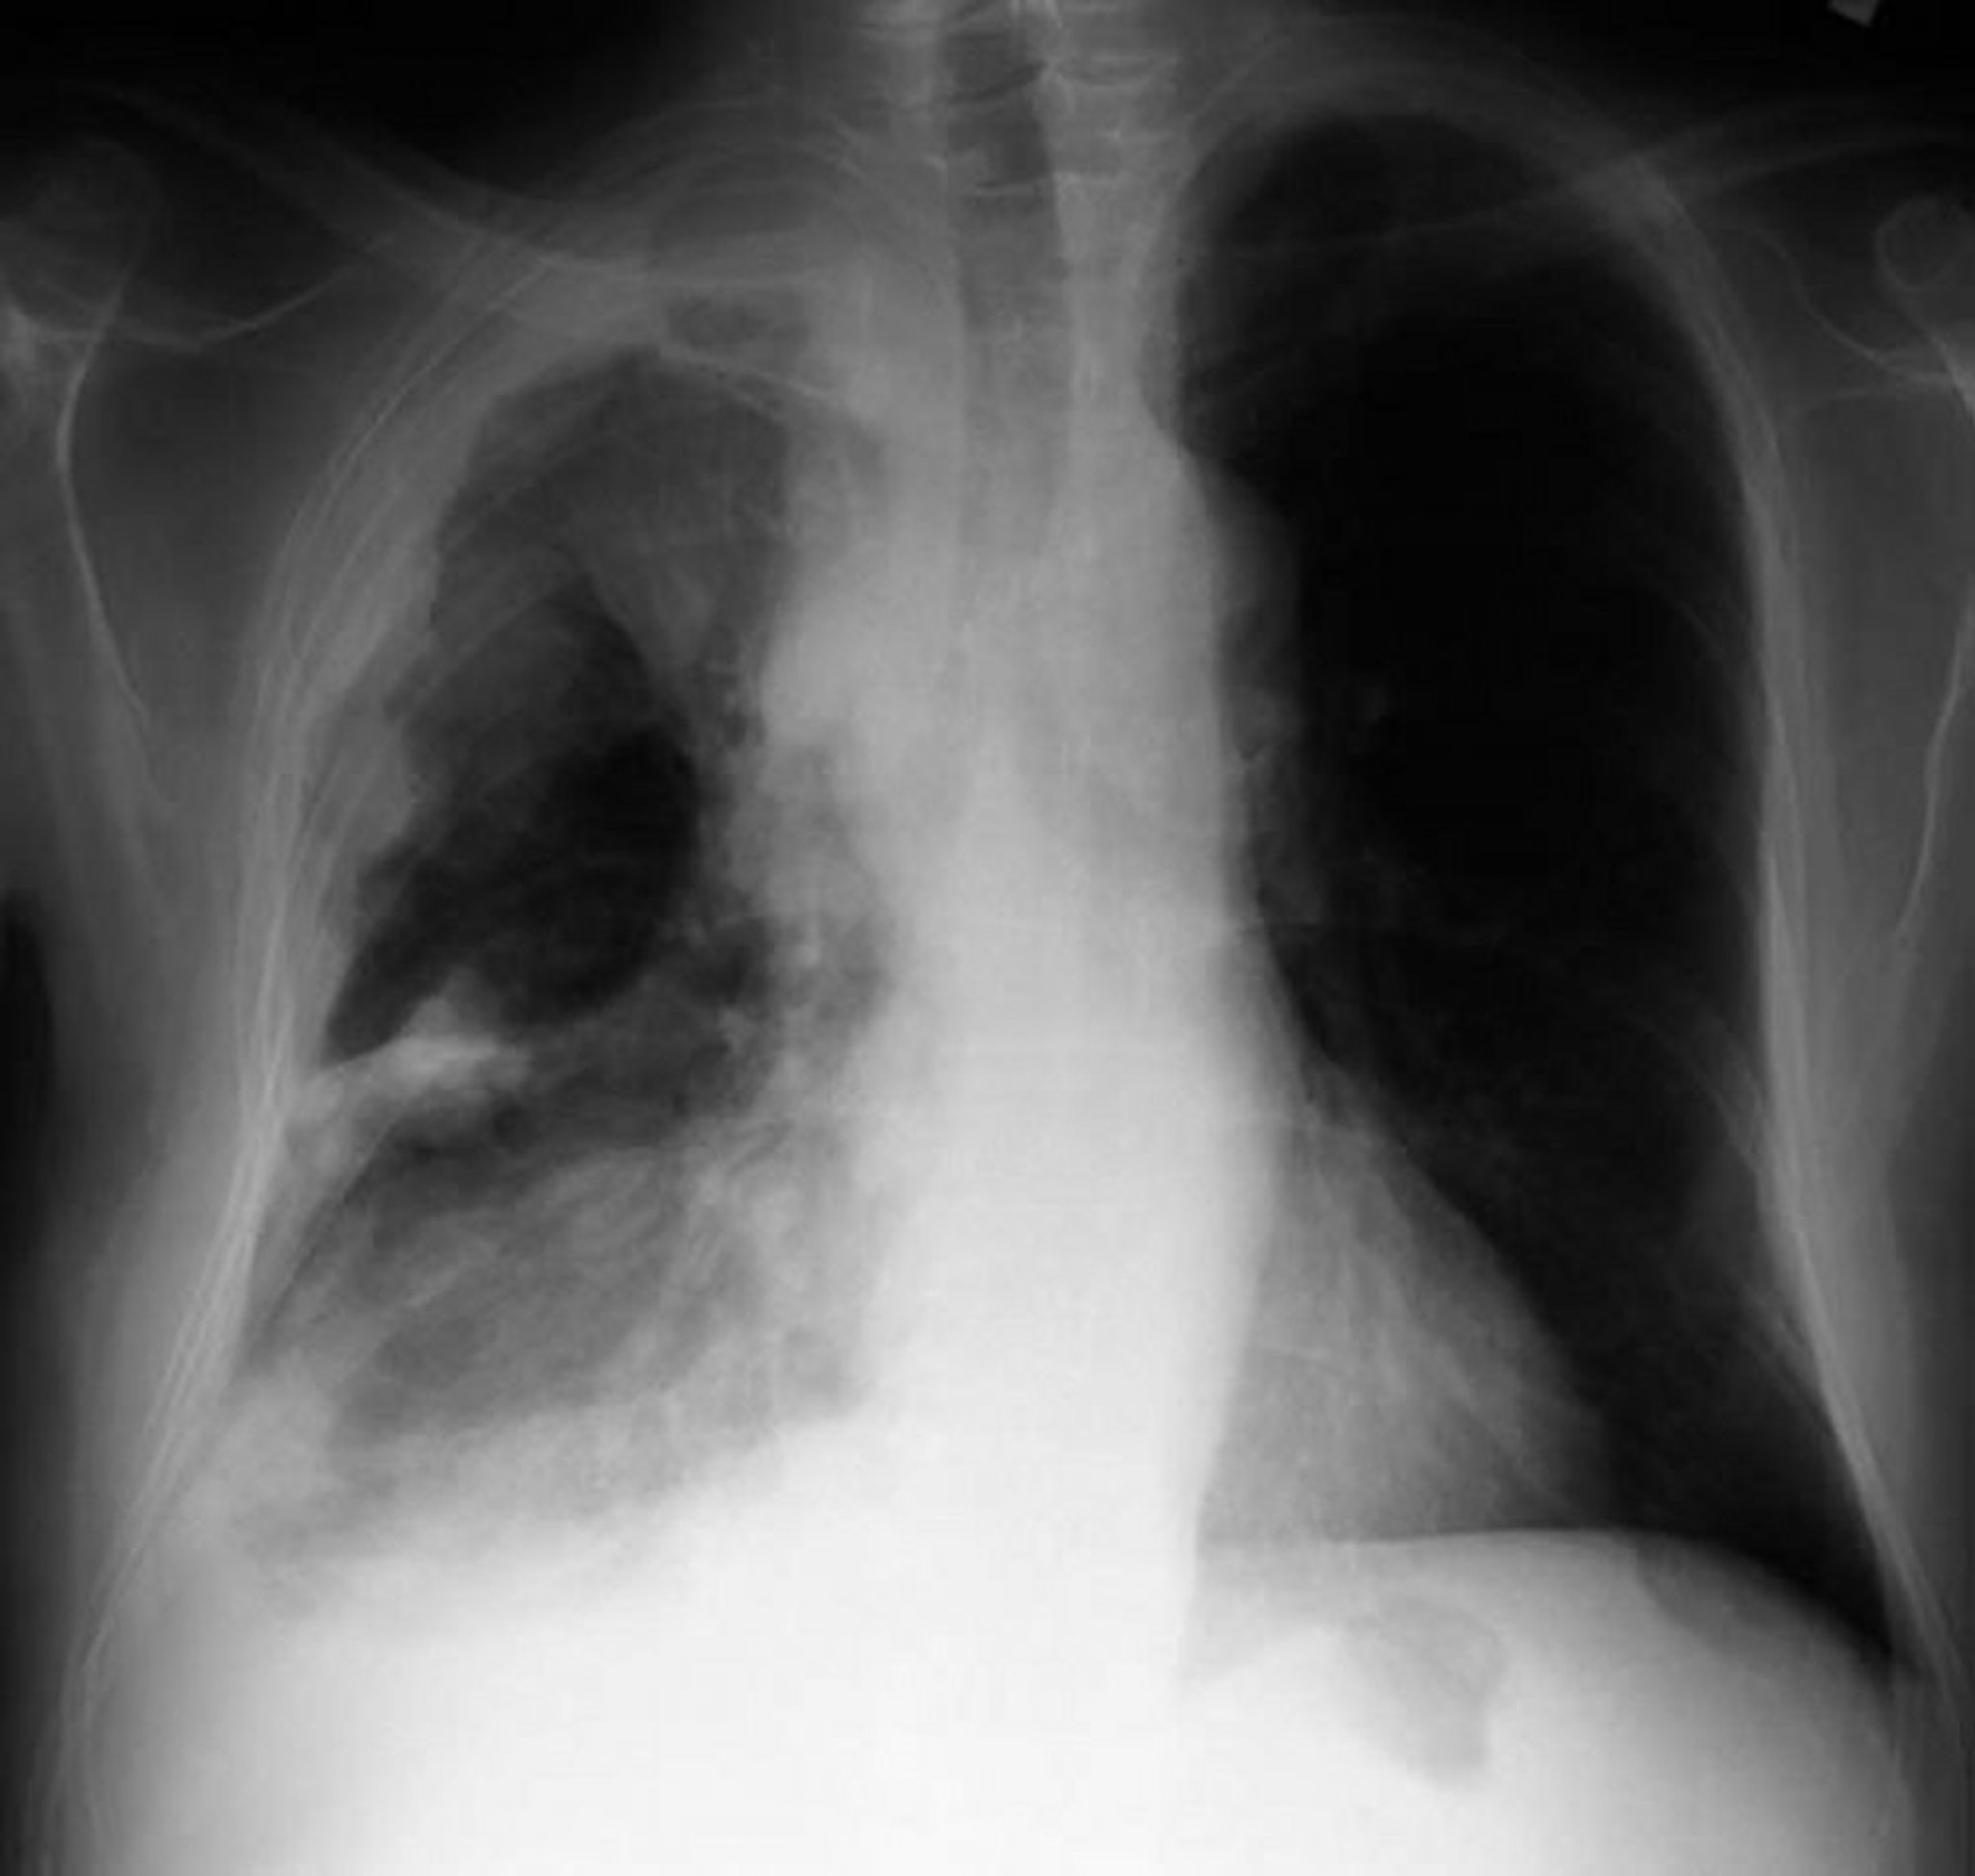

Мезотелиома плевры

Рентгенограмма грудной клетки у пациента с мезотелиомой плевры показывает утолщение плевры с узловыми образованиями на париетальной плевре.

By permission of the publisher. From Huggins J, Sahn S. In Bone's Atlas of Pulmonary and Critical Care Medicine. Edited by J Crapo. Philadelphia, Current Medicine, 2005.